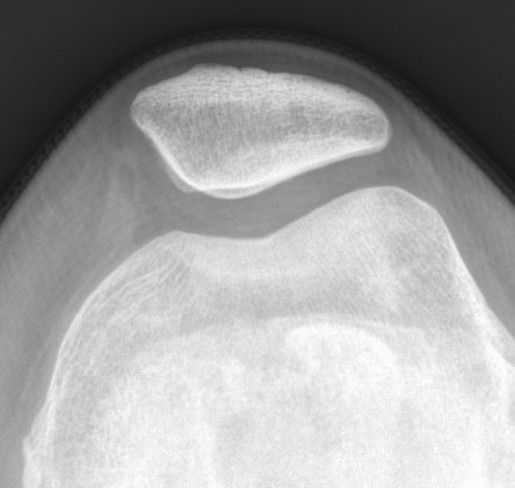

Patella subluxation

Patella should be well engaged in groove

Central ridge should lie at or medial to bisector of the trochlea groove

Patella well engaged in groove versus laterally subluxed patella